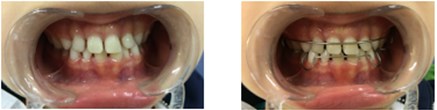

Early Correction Of Anterior Crossbite In Deciduous Dentition | RGUHS

journalgrid.com

journalgrid.com

Early Correction Of Anterior Crossbite In Deciduous Dentition | RGUHS

journalgrid.com

journalgrid.com